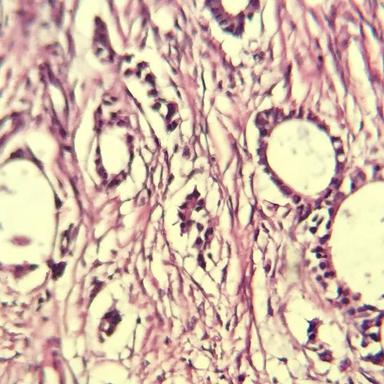

Invasive Ductal Carcinoma (IDC) Dataset

Our first prepared dataset is related to breast cancer, Invasive Ductal Carcinoma (IDC). This dataset has been collected from pathological biopsy samples of 150 patients (Grade I, II and III) who were referred to Anahid Clinic and Pour Sina Hakim Digestive Diseases Research Center, Isfahan University of Medical Science, during 2014-2019.

Each pathological sample in the dataset has four levels of magnification: 4x, 10x, 20x and 40x.

Magnification Samples

5x Magnification

10x Magnification

20x Magnification

40x Magnification